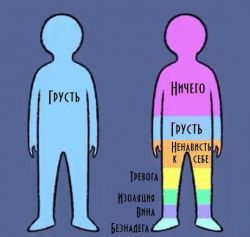

Защелачивание организма, или алкалоз, имеет множество причин, и его механизмы развития могут быть как внутриклеточными, так и системными. Известно несколько видов алкалозов: газовый, метаболический, выделительный, экзогенный и смешанный.